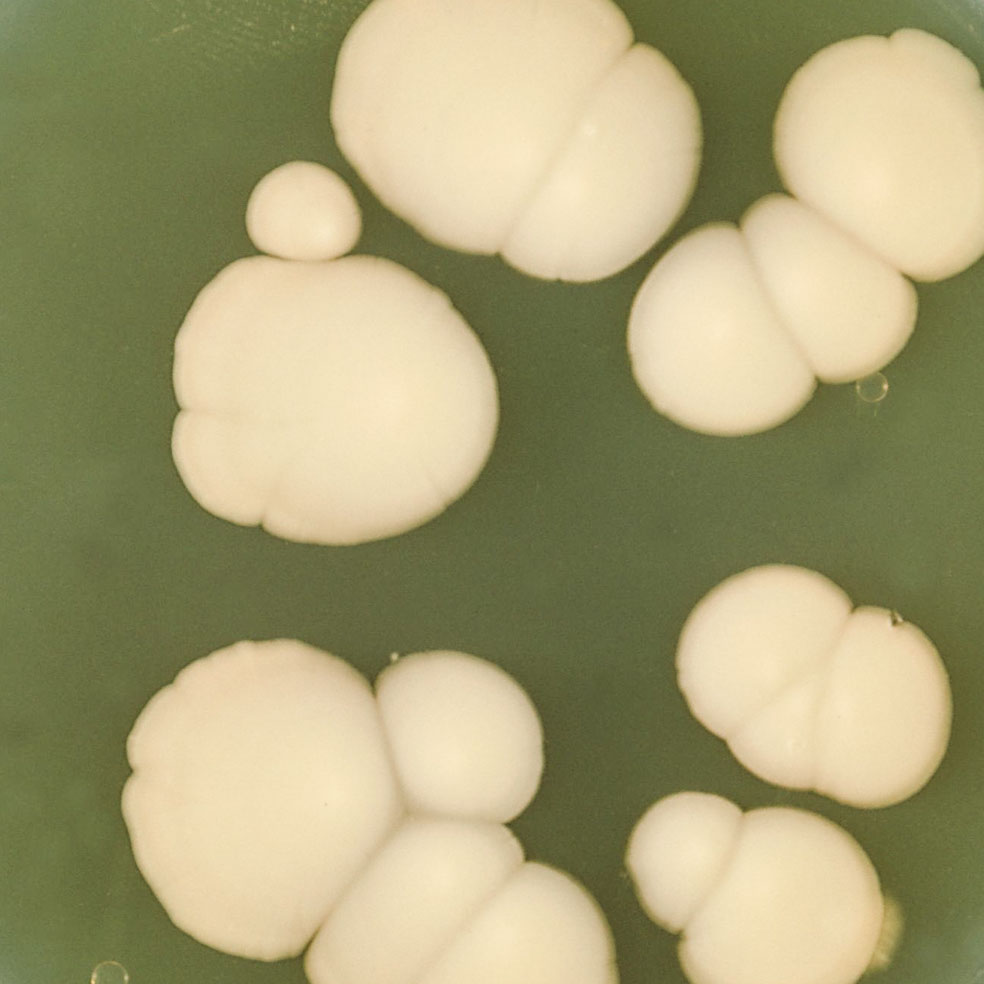

En la vagina viven bacterias que segregan ácido láctico para mantener a raya a otros microorganismos hostiles presentes en la flora vaginal, como la Candida albicans. Cuando se produce un desequilibrio, por alteraciones hormonales o el uso de algunos jabones, esta levadura entra en acción y causa vaginitis.